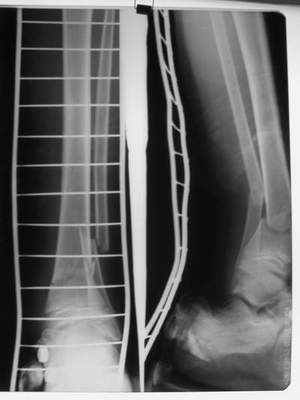

Перелом костей н\3 правой голени со смещением. Перелом большеберцовой кости можно охарактеризовать как компрессионно-оскольчатый.

Скелетное вытяжение за пяточную кость.

Первичные

Вытяжение

Фиксация

в гипсе